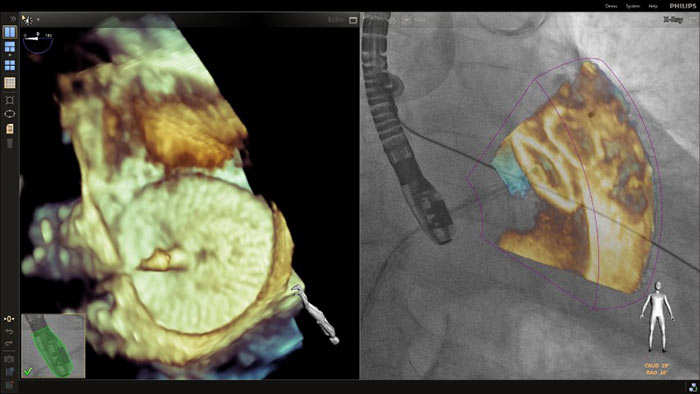

Au cœur de notre suite, la solution unique EchoNavigator est un bon exemple de l’engagement de Philips en faveur de la multimodalité et de l’intégration des processus de travail, en offrant les avantages des deux systèmes de la part du leader du secteur des solutions cardiaques interventionnelles par rayons X et par ultrasons.

Superposition ETO 3D temps réel du déploiement de l’occlusion de l’appendice auriculaire gauche avec EchoNavigator

Guidage de ponction transseptale à l’aide d’EchoNavigator